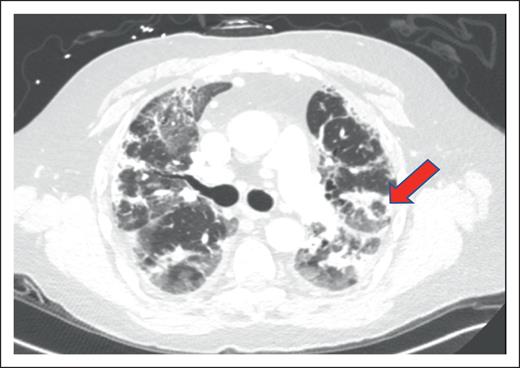

Radiological appearance of HCT-OP can be diverse, ranging from the classic atoll sign (Figure 2) to a combination of nonspecific ground-glass opacities and consolidation in peribronchovascular or subpleural distribution, with or without architectural distortion of the lung, resulting from fibrosis.19 HCT-OP can occur either unilaterally or bilaterally, as a single lesion or with multifocal consolidations without zonal preference.20,33 Rarely, HCT-OP may present as distinct nodular consolidation.34 If the clinical history and radiographic history are highly suggestive of HCT-OP and infectious workup is unrevealing, treatment for HCT-OP should be initiated.

Example of HCT-OP on CT scan of the chest. Noncontrast axial CT image, demonstrating multifocal consolidative and ground-glass pulmonary opacities. The atoll sign (arrowhead) can occasionally be seen and is characterized by central ground-glass opacity surrounded by dense consolidation, representing perilobular involvement, known as the reversed halo sign. Involvement in this case is predominantly peripheral, but HCT-OP can also be peribronchovascular, or occasionally nodular.